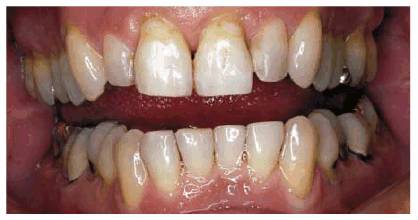

procedure can be seen in Figures 17-8A

and B 17-8C 17-8D 17-8E 17-8F 17-8G 17-8H and I, which show a 45-year-old man with

evidence of gingival and incisal abrasion, erosion, and abfraction. It is

Figure 17-8A and B: This 45-year-old man shows extreme tooth loss due to combination lesions both gingivally and incisally of abrasion, erosion, and abfraction.